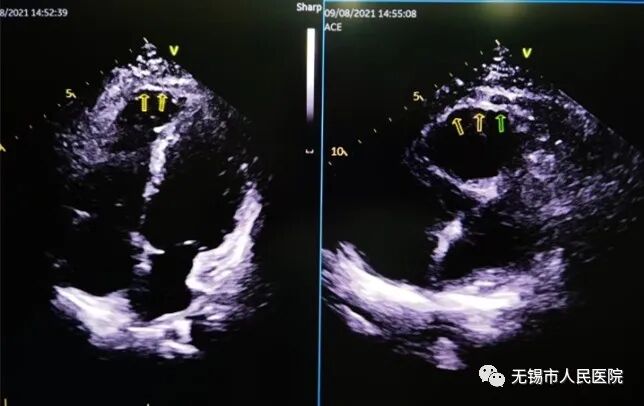

为了进一步明确诊断,过瑾立即带患者去心超室做检查。心功能科主任钱大钧反复仔细地查看,发现患者心脏右心室舒张末期内径扩大,右室游离壁菲薄呈羊皮纸样表现,活动性降低。钱大钧同样考虑是ARVC,建议患者进一步做心脏核磁共振检查。